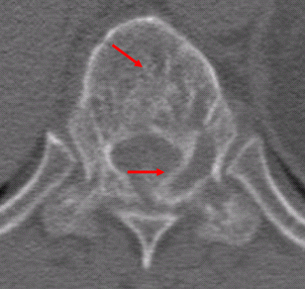

<흉추의

척추체와 후궁의 섬유주와 겉질뼈의 파괴가 관찰됨. 혈관종.>

척추경의 미란, 척추체의 파괴와 압박 골절 등을 볼 수 있습니다.

척추의 무기질침착과 겉질뼈의 상태를 정확히 파악하여 척추의 파괴 정도를 평가할 수 있습니다.

척추의 무기질침착과 겉질뼈의 상태를 정확히 파악하여 척추의 파괴 정도를 평가할 수 있습니다.